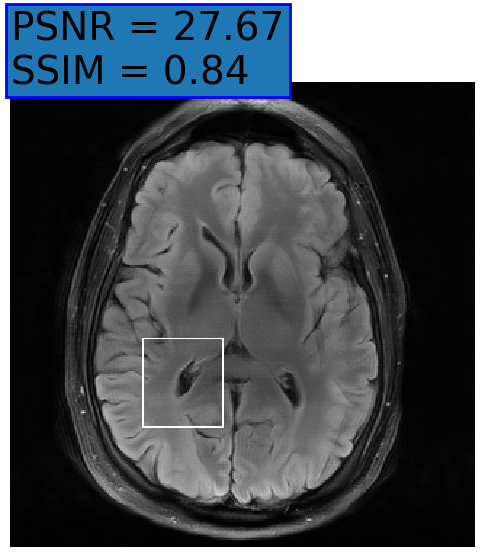

Figure 3: Examples of Reconstruction Results. Rows 1 and 3: The Ground truth (GT) fully sampled image, the reconstructed images obtained by the three models (1-3), NPB-REC, baseline, E2E-VarNet trained with Dropout, and the Std. map derived from our method for acceleration rates R=4𝑅4R=4, R=8𝑅8R=8, respectively. Rows 2 and 4: The corresponding annotated ROIS of the edema and resection cavity.

Fig. 3 presents examples of reconstruction results obtained by (1) our NPB-REC approach, (2) the baseline, and (3) Monte Carlo Dropout, for equispaced masks with two different acceleration rates R=4𝑅4R=4 and R=8𝑅8R=8. Table 1 presents the mean PSNR and SSIM metrics, calculated over the whole inference set, for the three models. our NPB-REC approach achieved significant improvements over the other methods in terms of PSNR and SSIM (Wilcoxon signed-rank test, pmuch-less-than\ll1e-4). The improvement in the reconstruction performance can be noted both quantitatively from the metrics especially for masks with acceleration rate R=8𝑅8R=8 and qualitatively via the images of annotations, where our results shows less smoothness than that obtained by Dropout.